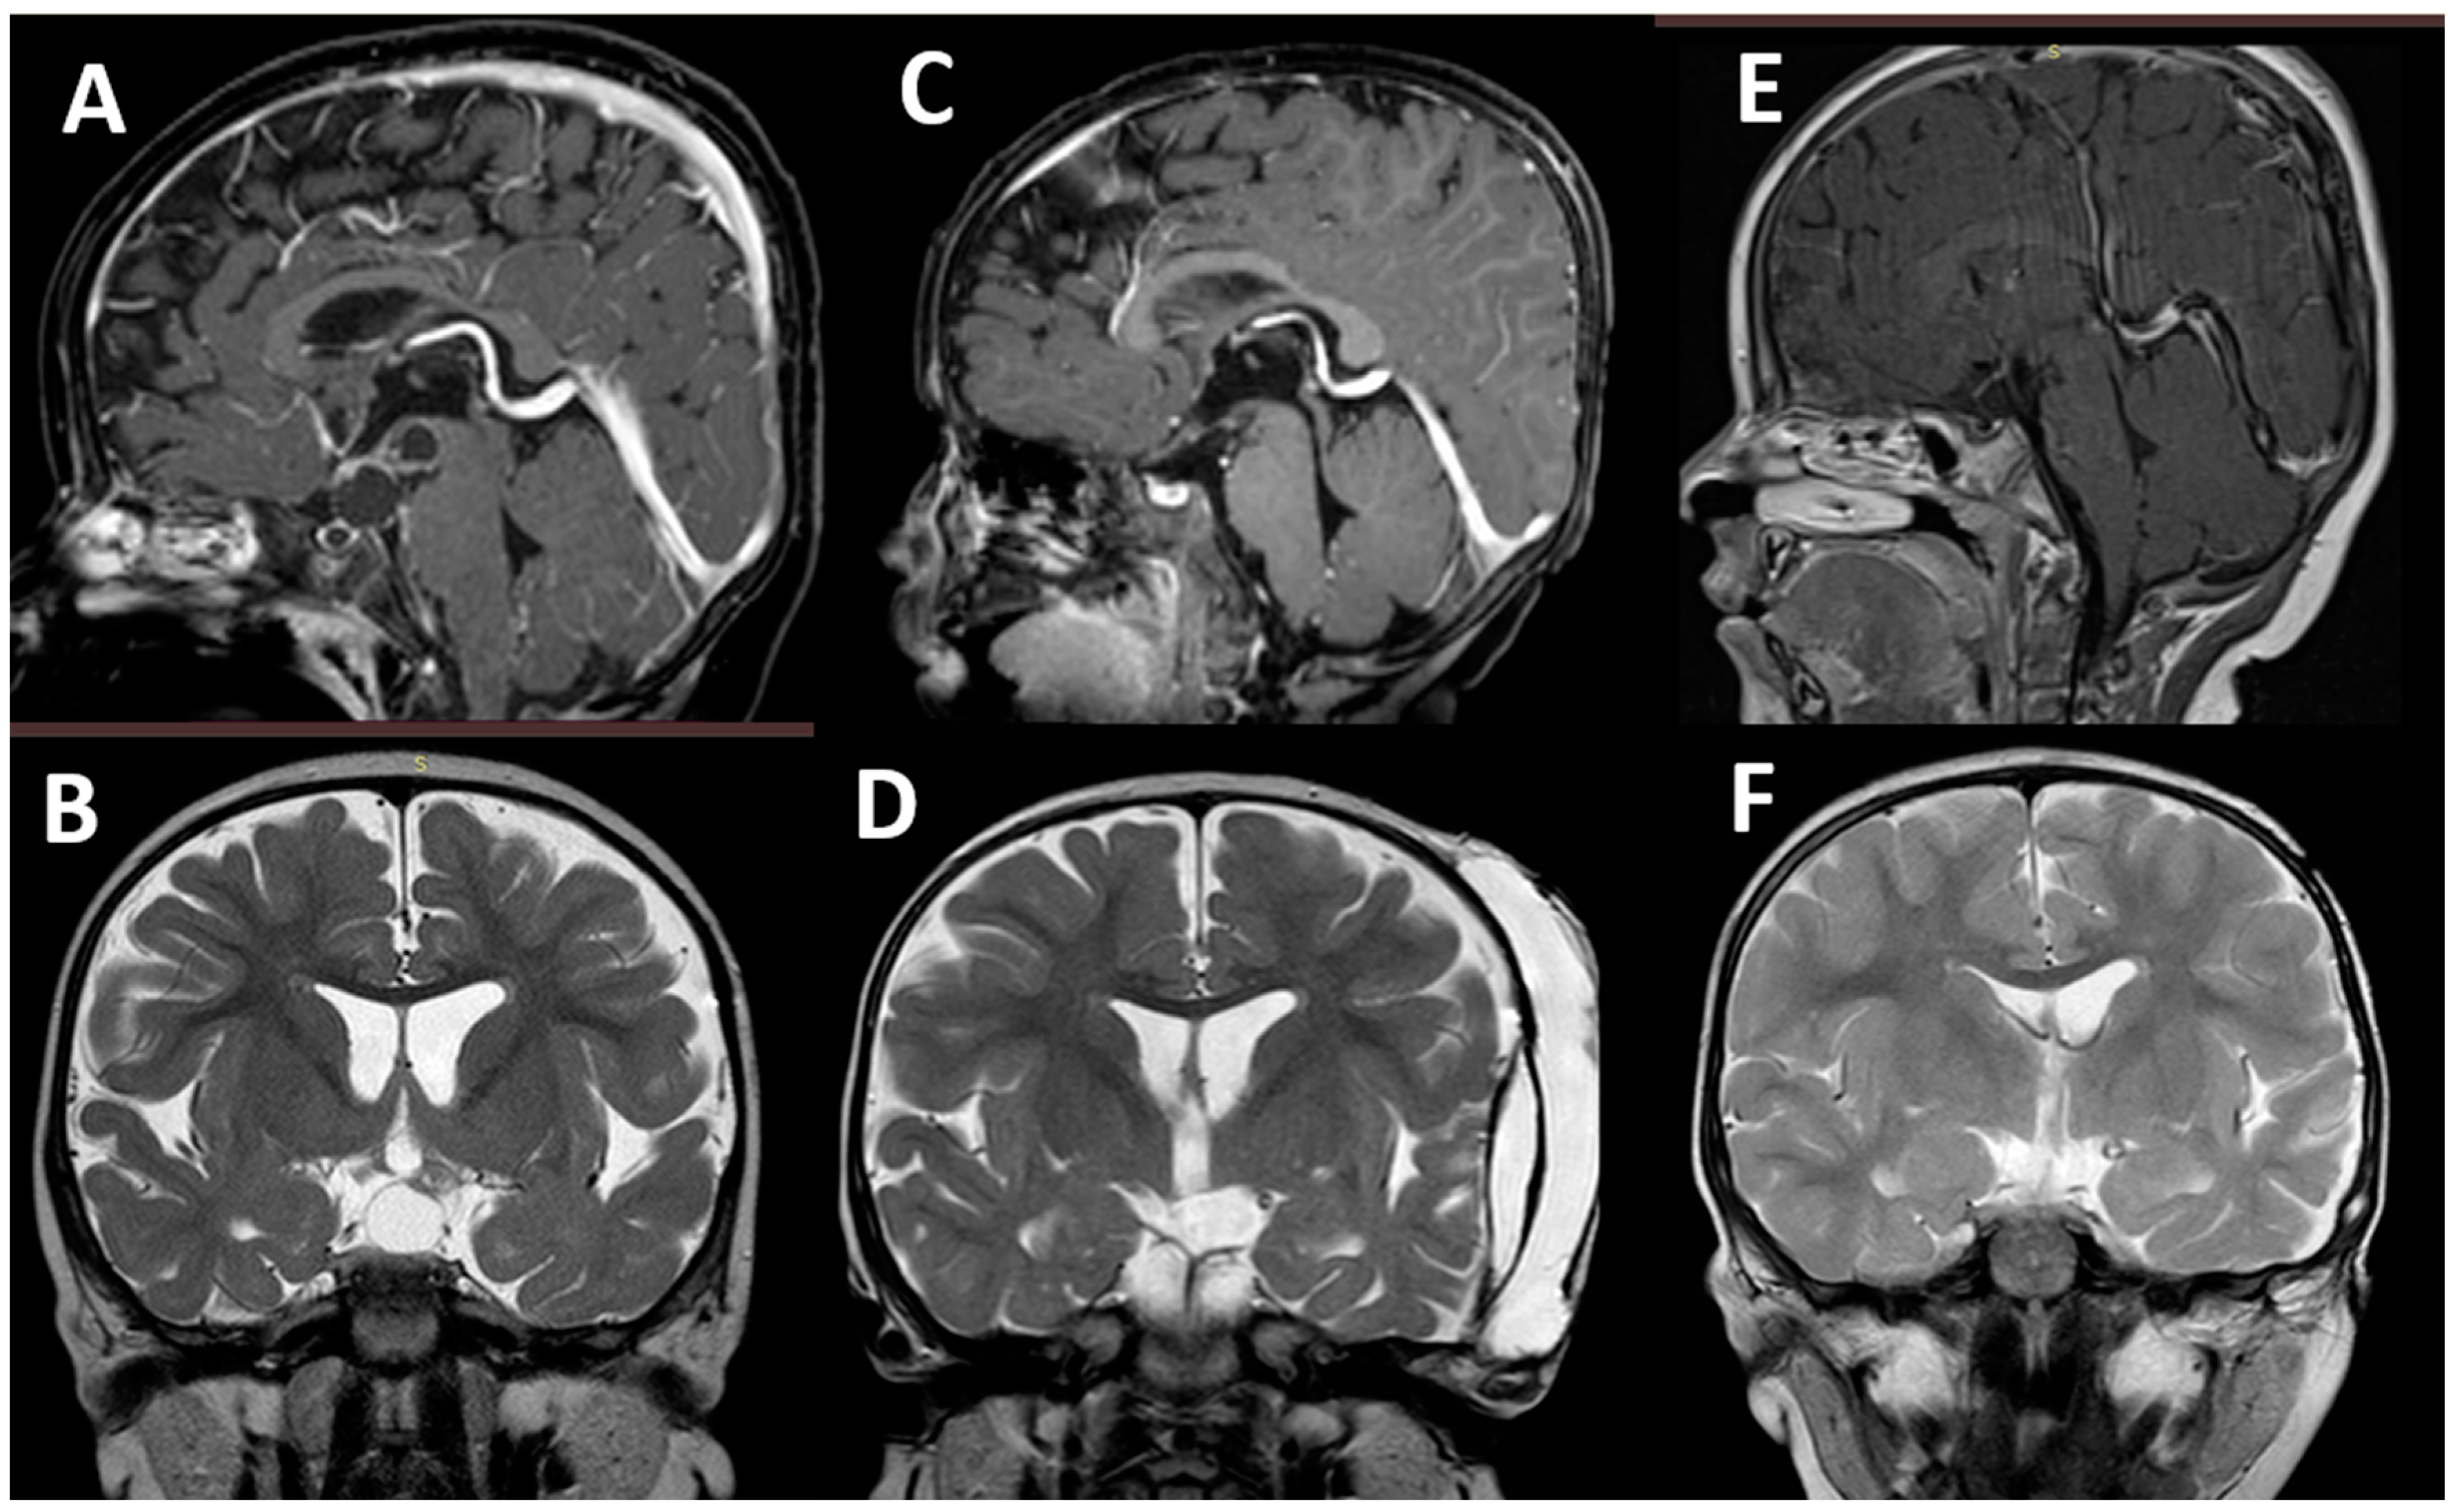

- Massimi, L.; Battaglia, D.; Bianchi, F.; Peraio, S.; Peppucci, E.; Di Rocco, C. Postoperative Epileptic Seizures in Children: Is the Brain Incision a Risk Factor? Neurosurgery 2018, 82, 465–472. [Google Scholar] [CrossRef] [PubMed]